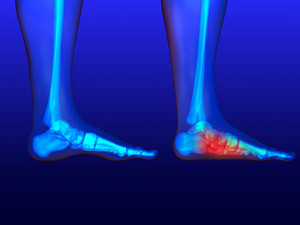

A dislocated toe occurs when the bones in the toe become misaligned, often leading to significant discomfort and mobility issues. Common symptoms include intense pain at the site of the injury, noticeable swelling, and bruising. The affected toe may appear deformed or out of place, and there may be difficulty moving it or walking without pain. Several factors contribute to dislocated toes, with sports injuries being a leading cause. Activities involving running, jumping, or sudden changes in direction can put excessive stress on the toe joints. Also, accidents such as stubbing the toe or dropping a heavy object on it can lead to dislocation. If you have sustained an injury that may have dislocated your toe, it is suggested that you promptly contact a podiatrist who can provide an accurate diagnosis and treatment.

Most severe toe pain is caused due to a sports injury, trauma from dropping something heavy on the toe, or bumping into something rigid. Other problems can develop over time for various reasons.

Toe pain can be caused by one or more ailments. The most common include:

- Trauma

- Sports injury

- Sprains

- Fractures (broken bones)

- Dislocations

In many cases the cause of toe pain is obvious, but in others, a podiatrist may want to use more advanced methods to determine the problem. These can range from simple visual inspections and sensation tests to X-rays and MRI scans. Prior medical history, family medical history, and any recent physical traumatic events will all be taken into consideration for a proper diagnosis.

Treatments for toe pain and injuries vary and may include shoe inserts, padding, taping, medicines, injections, and in some cases, surgery. If you believe that you have broken a toe, please see a podiatrist as soon as possible.

What to Know About a Broken Toe

The forefoot is composed of five metatarsal bones and fourteen phalanges. Each toe has three bones, except for the big toe which only has two. Our toes play an essential role to the walking process, which is why a broken toe could seriously disrupt one’s ability to move around. Toe fractures are common and can be very painful. Fortunately, these injuries rarely require surgery and usually heal with rest and a change in activity.

Broken toes typically result from a traumatic event such as falling, stubbing the toe, or dropping something on the toe. Traumatic toe fractures may be categorized as either minor or severe fractures. At times, one may hear a “pop” or “crack” sound when the bone breaks. Common symptoms of a traumatic toe fracture include pain, throbbing, bruising, swelling, and redness.

Another type of fracture is usually of the metatarsal, which is behind the toes and these bones can have stress fractures. These injuries usually appear in the form of small hairline breaks on the bone. Stress fractures develop after repetitive activity.

If you suspect that you have a broken toe, you should make an appointment with Dr. DiNucci. He will likely diagnose you by performing a physical exam and an X-ray. Treatment for a broken toe may include the R.I.C.E. method, buddy taping, surgery, or antibiotics. The R.I.C.E. method (Rest, Ice, Compression, and Elevation) is a common treatment method for many injuries because it decreases pain. Buddy tapping involves wrapping the injured toe next to an adjacent toe to keep it supported and protected. These two methods have proven to be effective in the healing process for toe fractures. The estimated healing time for a broken toe is approximately four to six weeks. If the injury becomes infected or requires surgery, the estimated healing time may take eight weeks or more.